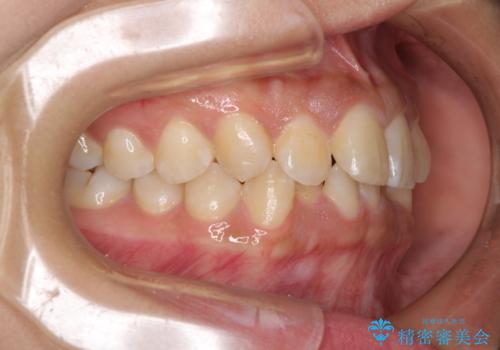

前歯のデコボコと隠れてしまう下顎前歯 インビザラインですっきりと改善

インビザライン発注後に長期滞在先から2年間ほど帰国することができず、インビザラインの有効期限内に終了できるのか不安でしたが、矯正治療開始後は十分な装着時間を達成され、1年未満の期間で無事に終えることができました。